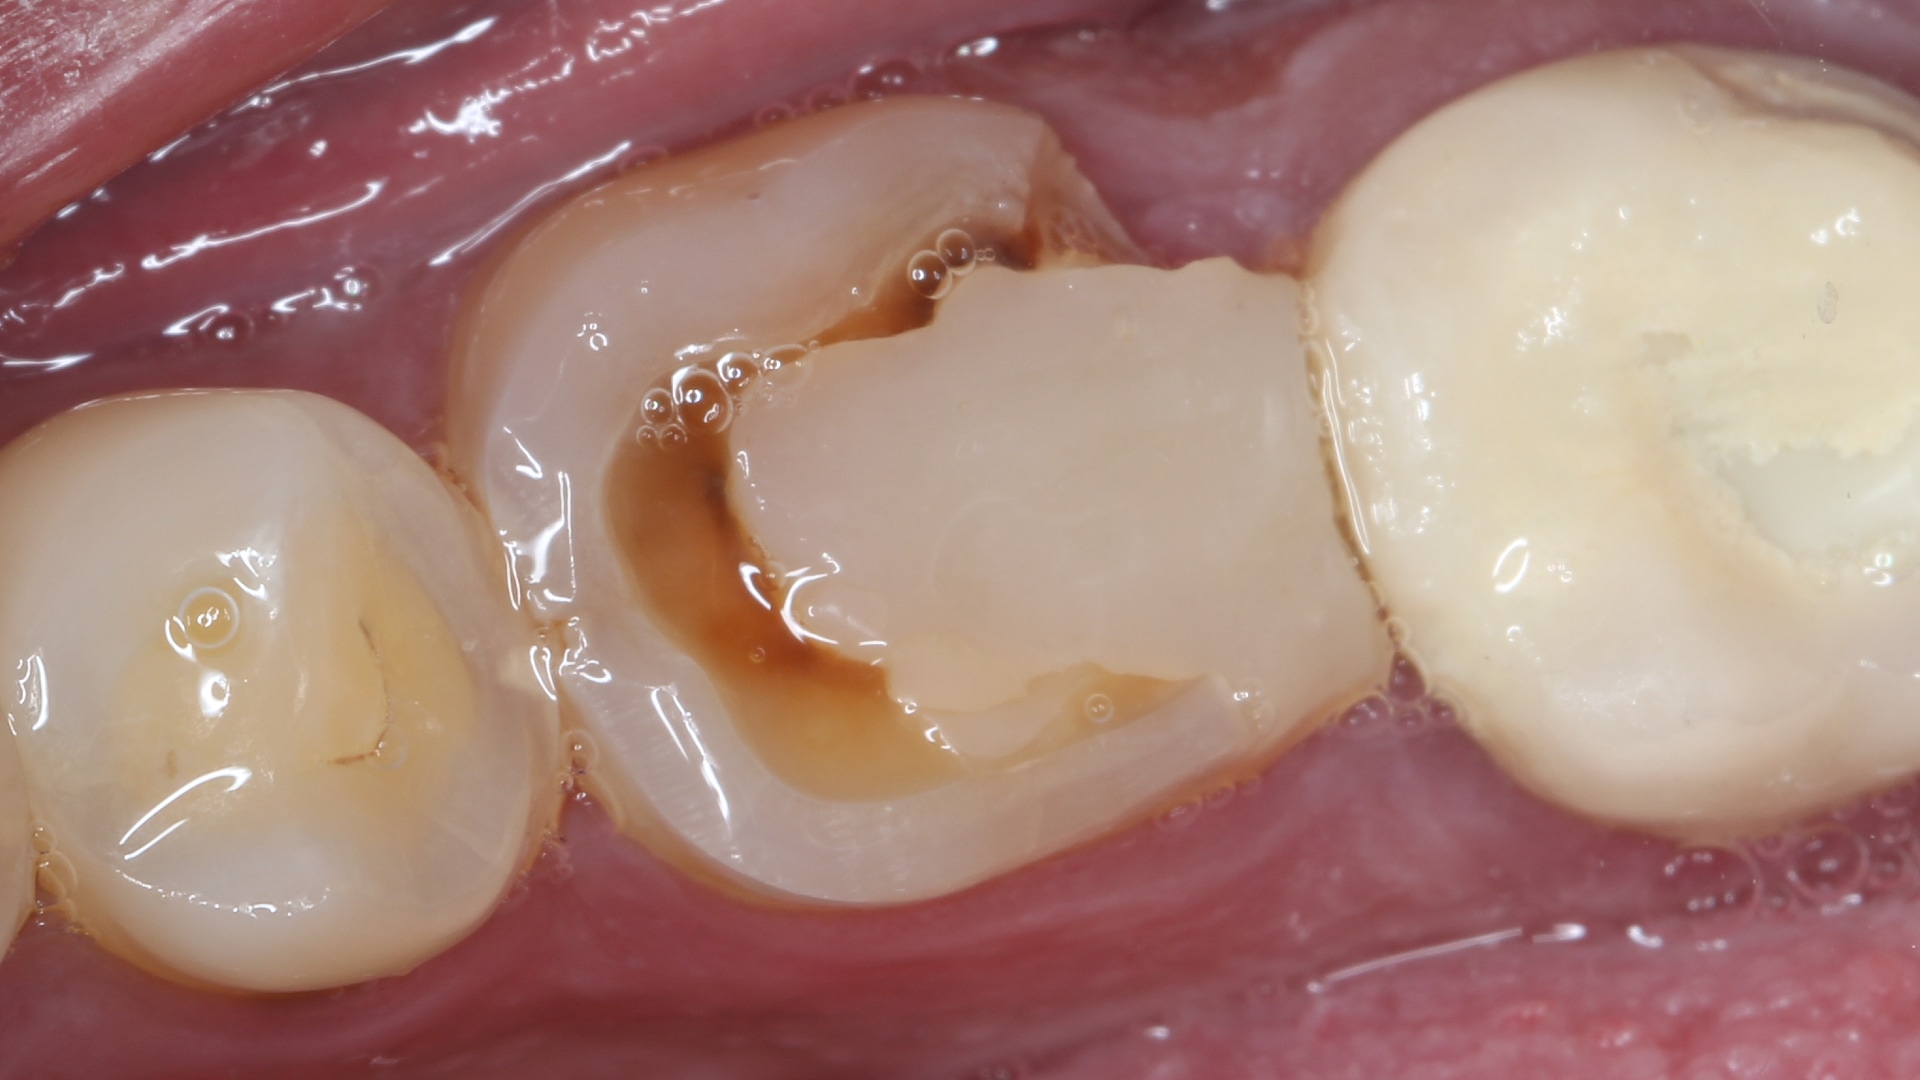

Faulty composite replacement Picture

By Dr.Dina EzzeldinAdded on January 2026

Faulty composite replacement

Sometimes indirect restorations are the answer

Patient presented with an old composite restoration in an endodontically treated tooth which caused him discomfort in occlusion along with gingival ir...

Read More